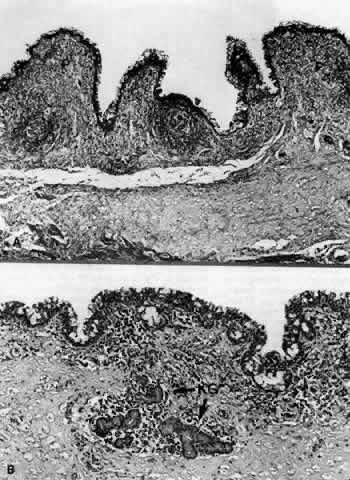

Fig. 1. Low-power view of the globe. A. Arrow pointing to the region of the superior fornix. B. Superior fornix (F) showing epithelium and substantia propria. Conjunctival sac (CS). C. Higher-power view of epithelium showing goblet cells on the surface (arrows). (B, × 50; C, × 170)

Fig. 2. A. Region of the inferior fornix (arrow). B. Inferior fornix showing epithelium, goblet cells, and a follicle (F). C. Inferior fornix showing Müller's muscle (MM) in the substantia propria. (B, × 60; C, × 80)

Fig. 7. A. Inferior fornix showing papillary projection (P). B. Inferior fornix demonstrating Krause's glands (KG). (A, × 40; B, × 80)